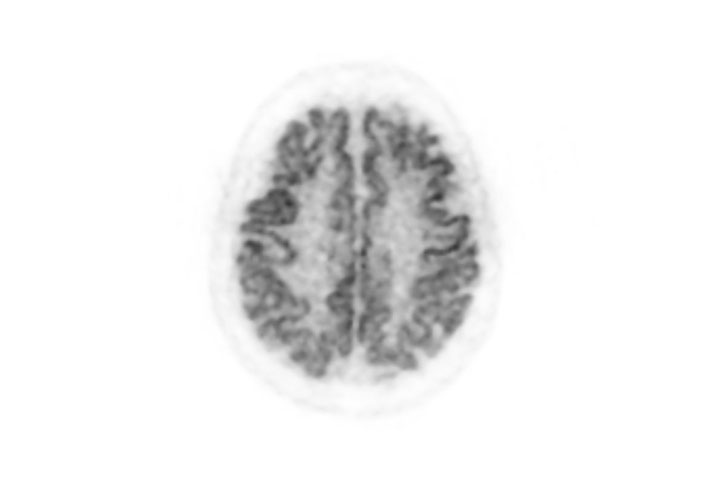

Fusion image of PET and MRI